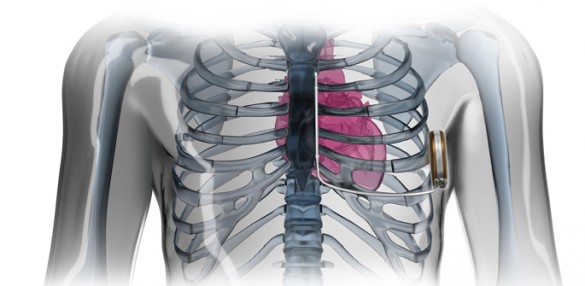

An implanted infusion pump for chronic pain is covered by Medicare when used to 1) administer opioid drugs, singly or in combination with other opioid or non-opioid drugs, 2) intrathecal or epidural route; 3) for treatment of severe chronic intractable pain of malignant or nonmalignant origin in patients who have a life expectancy of at least three (3) months, and 4) the pain has been proven to be unresponsive to less invasive medical therapy. In order to be considered medically reasonable and necessary, all of the following criteria must be met and clearly documented in the beneficiary’s medical record:.